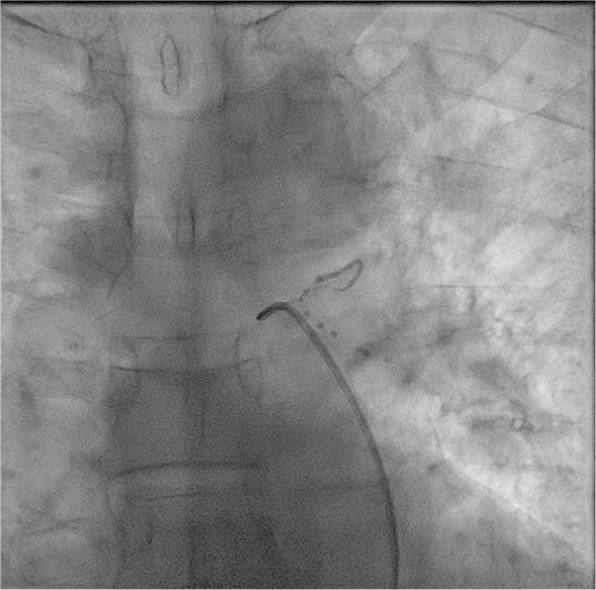

Abstract Image